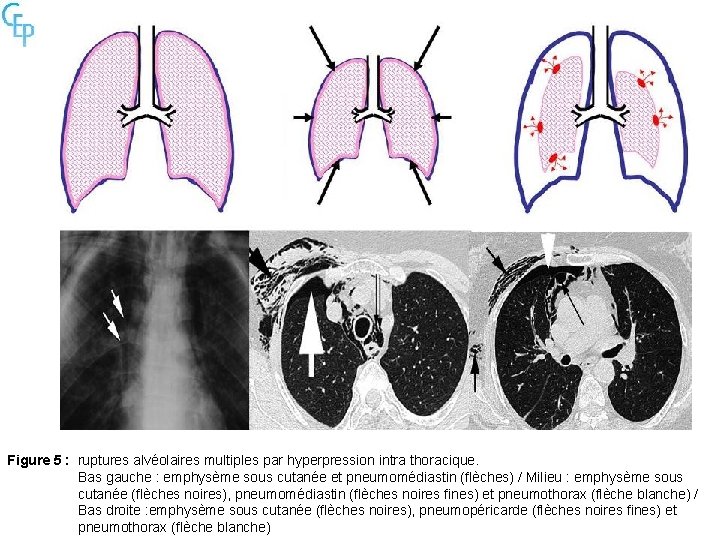

Figure 5 : ruptures alvéolaires multiples par hyperpression intra thoracique. Bas gauche : emphysème sous cutanée et pneumomédiastin (flèches) / Milieu : emphysème sous cutanée (flèches noires), pneumomédiastin (flèches noires fines) et pneumothorax (flèche blanche) / Bas droite : emphysème sous cutanée (flèches noires), pneumopéricarde (flèches noires fines) et pneumothorax (flèche blanche)